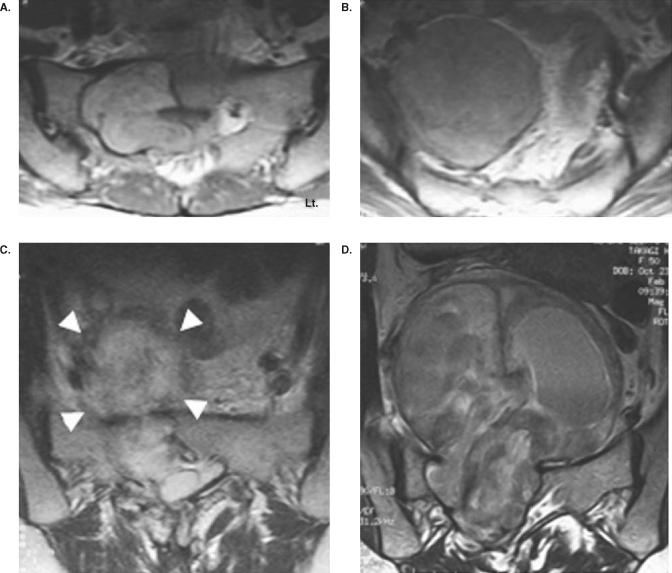

Sacral and presacral schwannomas are often found incidentally, because they present with vague symptoms or symptomless. Schwannoma occurring in this area occasionally presents with enormous dimensions, known as a giant schwannoma. The tumor removal is a surgical challenge due to the difficult approach and abundant vascularity. The aim of this study is to review cases of giant sacral schwannomas focusing the surgical management and outcome. Six patients with sacral and presacral schwannoma were treated surgically. The patients included two males and four females, and the mean age was 47.8 years. All patients experienced pain at the time of presentation. The tumors were classified as intraosseous type in one case, dumb-bell type in four cases, and retroperitoneal type in one case. The tumors were removed with a piecemeal subtotal excision in three patients, a partial excision in two patients, and enucleation in one patient. The surgeries were performed by the combination of an anterior and posterior approach in three patients, a posterior approach in two patients, and an anterior approach in one patient. The mean surgical time was 7.8 hrs, and the mean blood loss was 2572 g. The tumor recurred in one patient after the partial excision and was removed completely in a second surgery. No patient, including the patient who underwent the second surgery, presented with pain and obvious neurological deficit at the final follow-up. The surgical treatment of the giant sacral schwannoma with a piecemeal subtotal excision can achieve a good outcome, avoiding unnecessary neurological deficit.